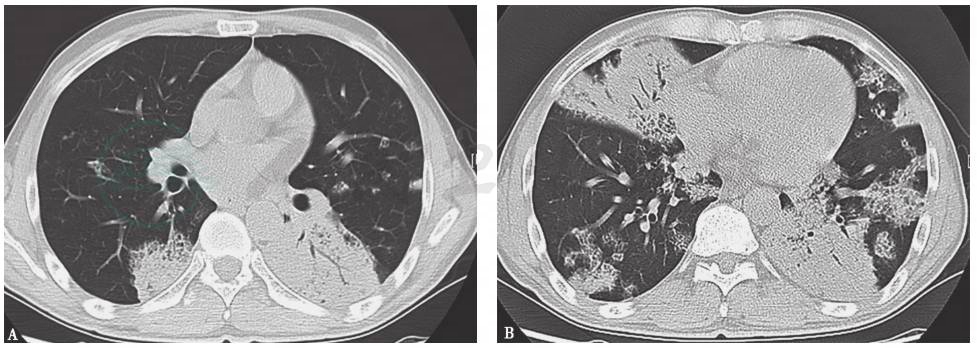

特殊感染:本例患者外观消瘦,双肺多发病变,抗感染治疗后病情反复,须注意排除肺结核,尤其肺结核所致干酪性肺炎(图3、图4)。肺结核的胸部影像学表现可为实变,密度多不均匀(中心密度高,边缘模糊),其中可有多个融合区,好发于上叶尖后段和下叶背段,病变肺段体积缩小,胸廓塌陷,大多数同时可见空洞、钙化、卫星灶等,由于沿支气管传播,病变多在相邻的多叶段内。本例患者的胸部影像学表现与此不符,可进一步查PPD、T-SPOT检测、痰抗酸染色等以排除该病。

图3 干酪性肺炎胸部影像学表现

胸部CT可见右上肺大片高密度实变影,伴支气管充气征

图4 干酪性肺炎胸部影像学表现

胸部CT可见双中下肺可见较弥漫斑片状高密度影,病灶沿支气管分布,并见树芽征